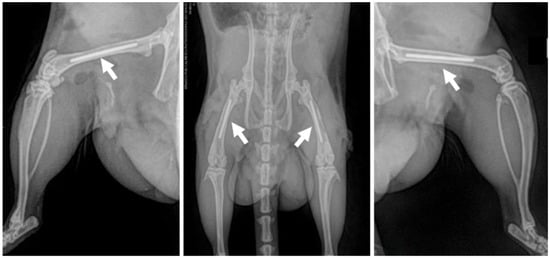

2.3. Surgical Procedure and Post-Operative Care

2.4. Post-Operative Tissue Harvesting